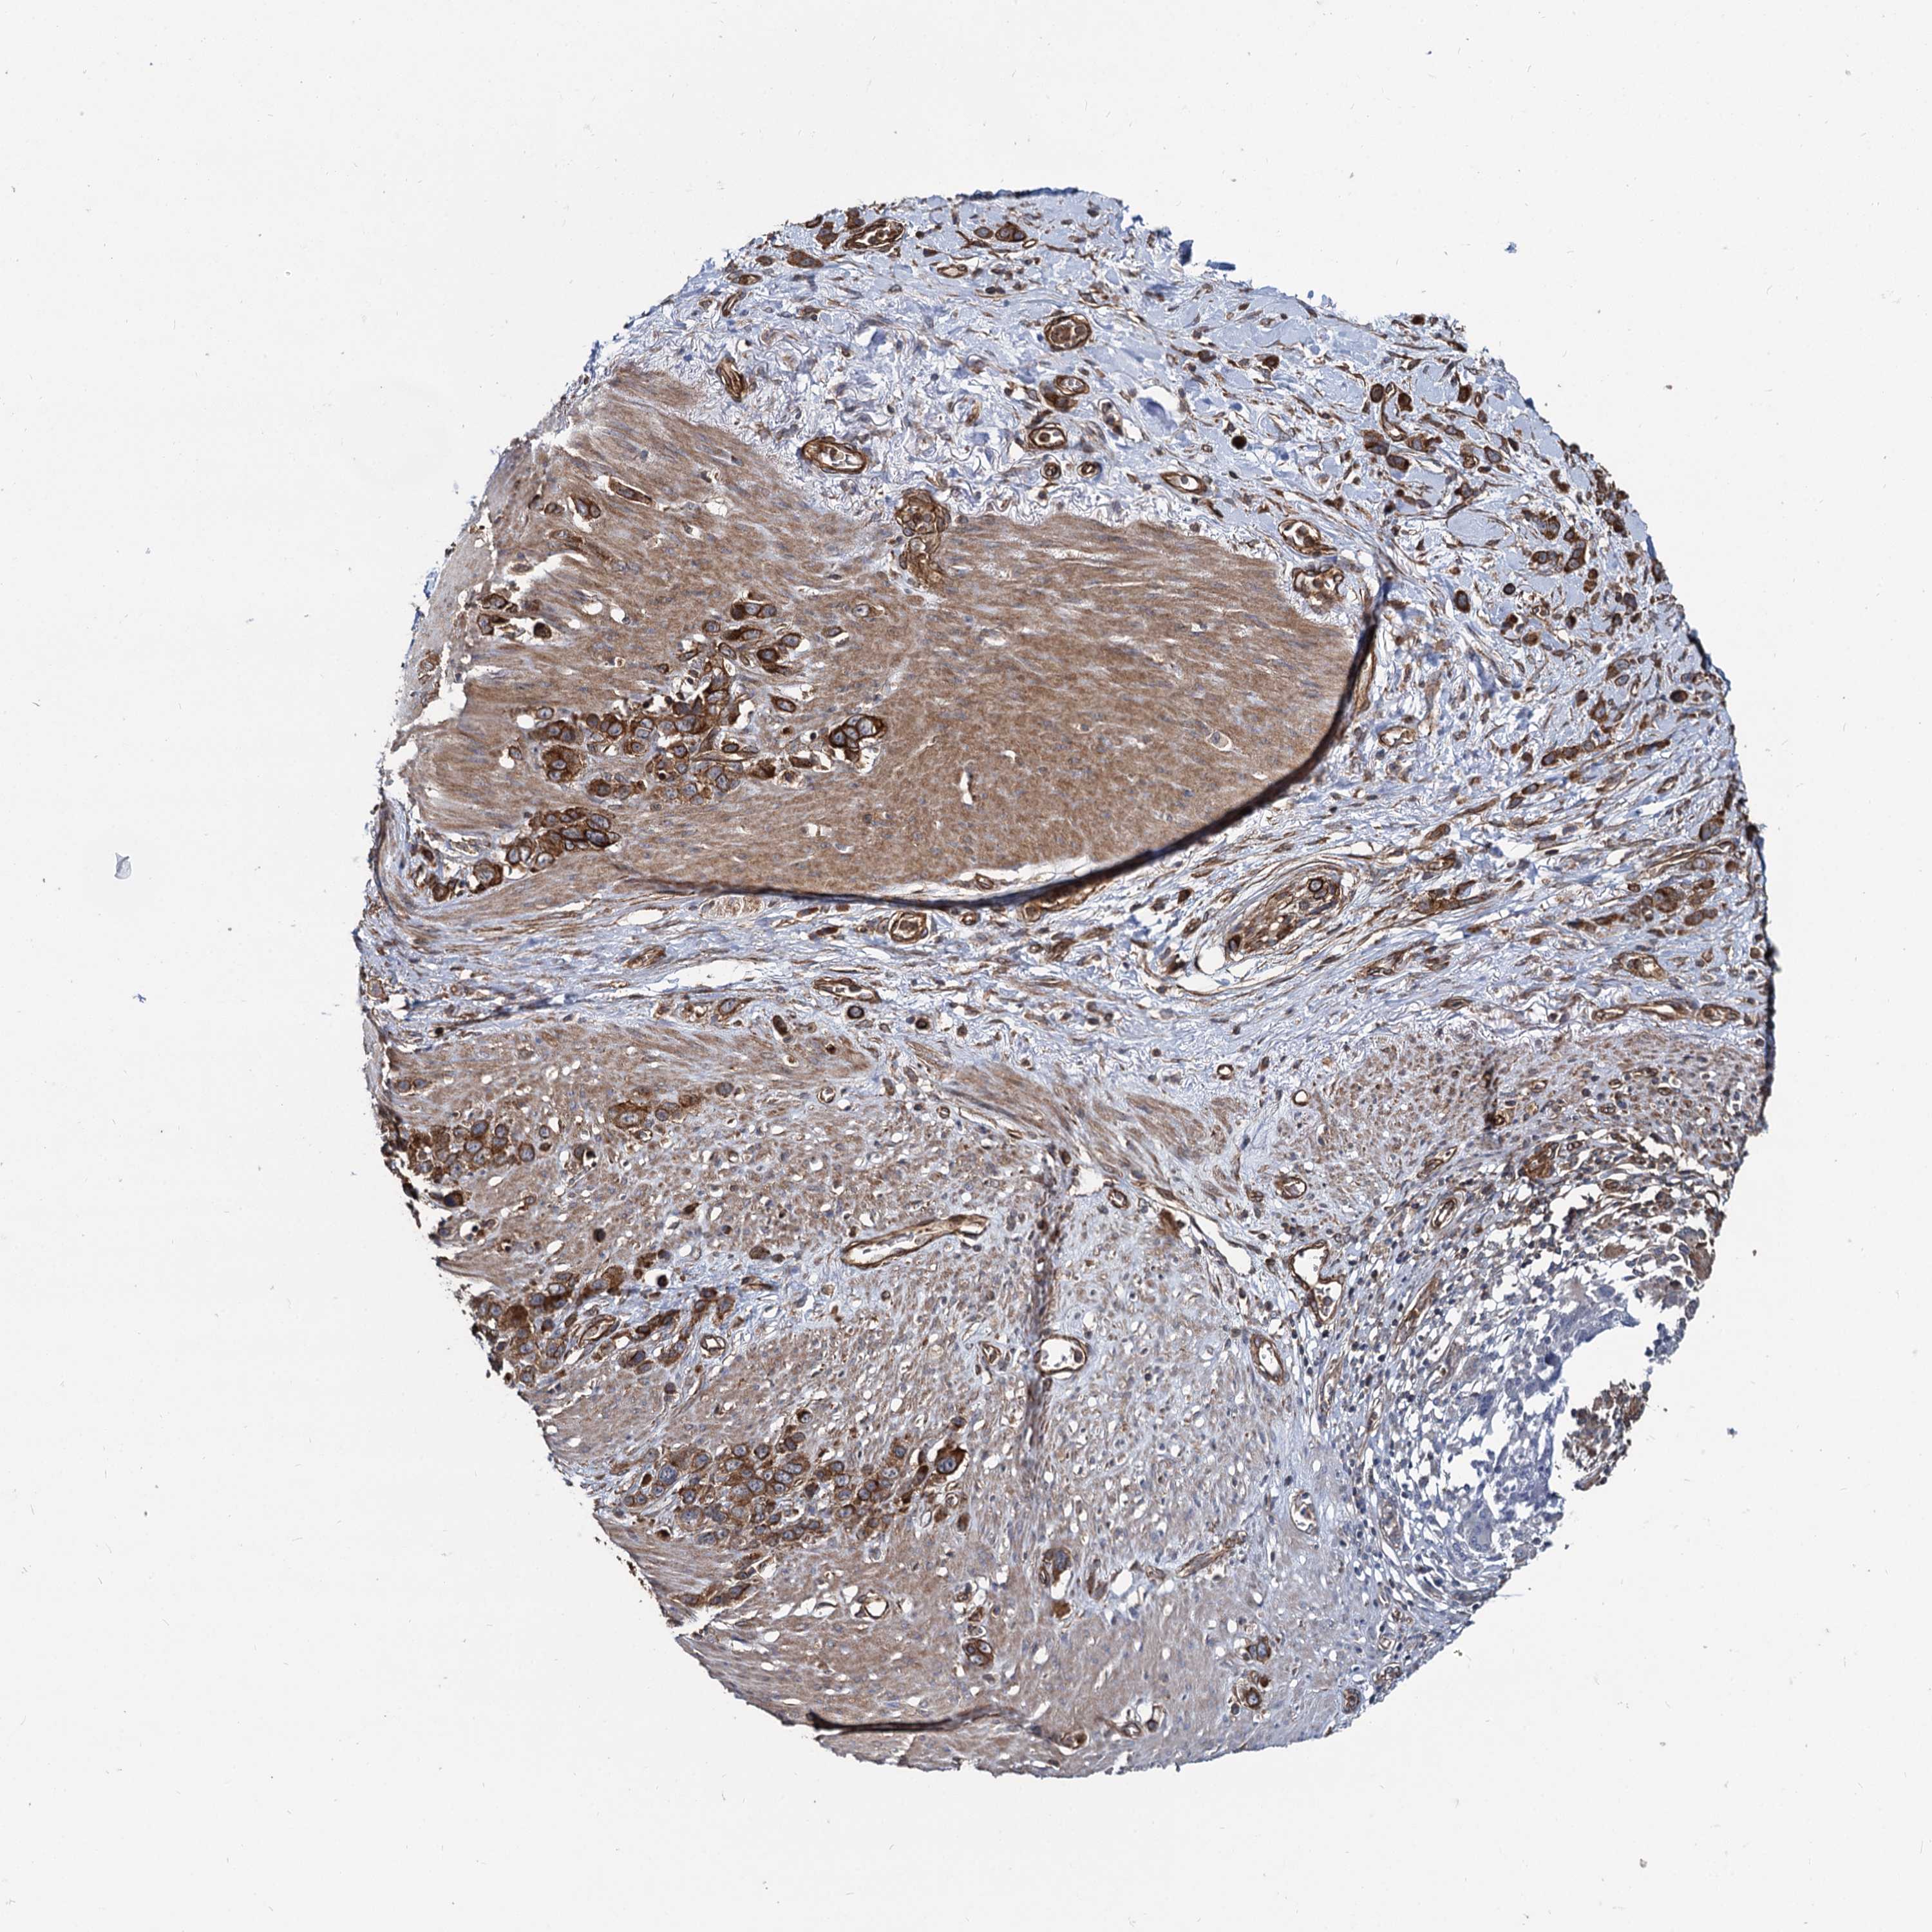

STOMACH CANCER - Protein expressioni

A mouse-over function shows sample information and annotation data. Click on an image to view it in a full screen mode. Samples can be filtered based on level of antibody staining by selecting one or several of the following categories: high, medium, low and not detected. The assay and annotation is described here.

Antibody stainingi

Antibody staining in the annotated cell types in the current human tissue is reported as not detected, low, medium, or high, based on conventional immunohistochemistry profiling in selected tissues. This score is based on the combination of the staining intensity and fraction of stained cells.

Each image is clickable and will lead to virtual microscopy that enables deeper exploration of all samples and also displays staining intensity scores, fraction scores and subcellular localization as well as patient and tissue information for each sample.

Antibody HPA039807

Staining

High

Medium

Low

Not detected

Intensity

Strong

Moderate

Weak

Negative

Quantity

>75%

75%-25%

<25%

None

Location

Nuclear

Cytoplasmic/membranous

Cytoplasmic/membranous,nuclear

Adenocarcinoma, NOS

Adenocarcinoma, High grade